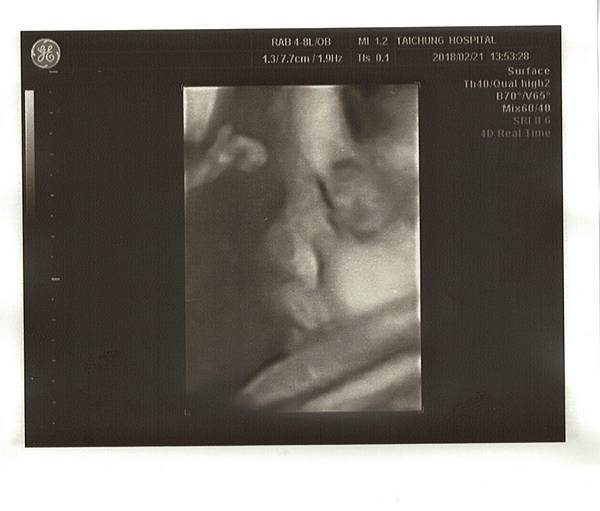

23W5D產檢日,寶寶體重886g,醫生說一切都很標準,寶寶似乎大了兩週呢!

這次的4D照好清楚喔!鼻子、嘴巴長得超像Chris!!連醫生都說比較像爸爸~呵呵

而且寶寶這次胎位轉正囉!!關於陰部疼痛的問題,我再次問了劉醫師,劉醫師說如果有點腫腫的,應該是靜脈曲張,開了一條凝膠給我擦在會疼痛的地方~